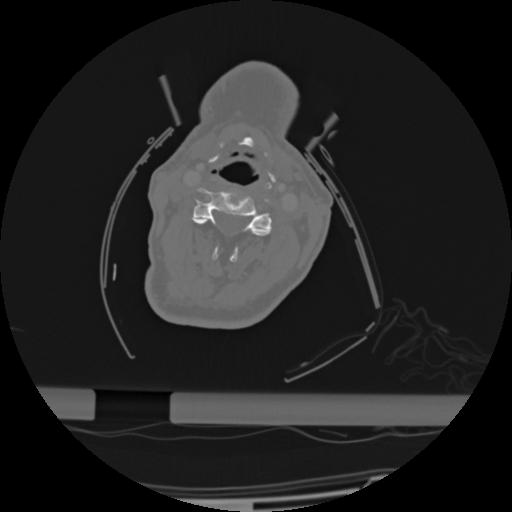

22 ANGIO,CE,Vol,0.5,ANGIO,,